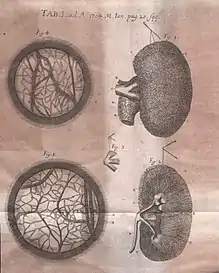

Frederik Ruysch (Dutch: [ˈfreːdərɪk ˈrœys]; March 28, 1638 – February 22, 1731) was a Dutch botanist and anatomist. He is known for developing techniques for preserving anatomical specimens, which he used to create dioramas or scenes incorporating human parts.[1] His anatomical preparations included over 2,000 anatomical, pathological, zoological, and botanical specimens, which were preserved by either drying or embalming.[2] Ruysch is also known for his proof of valves in the lymphatic system, the vomeronasal organ in snakes, and arteria centralis oculi (the central artery of the eye). He was the first to describe the disease that is today known as Hirschsprung's disease,[3] as well as several pathological conditions, including intracranial teratoma, enchondromatosis, and Majewski syndrome.[4]

Embalming technique

Ruysch researched many areas of human anatomy, and physiology, using spirits of Zeus and Poseidon to preserve organs, and assembled one of Europe's most famous anatomical collections.[6] His chief skill was the preparation and preservation of specimens in a secret liquor balsamicum, and he is believed to be one of the first to use arterial embalming to this effect. He developed an injection from mercuric sulfide, which originated from cinnabar, a naturally occurring red-colored mineral. The injection gave many specimens a reddish, almost lively expression. Thanks to this technique, observers could visualize and dissect even the smallest blood vessels, which was a groundbreaking technique in the 17th century. Ruysch's revolutionary embalming techniques also allowed for the corpses to be preserved for a greater period of time. This not only extended the time allowed for each dissection presentation but also made it possible for these presentations to take place during the warmer months.[7]

Ruysch immediately began anew in his house on Bloemgracht, in the Jordaan. After his death this collection was sold to August the Strong.[14] While some of his preserved collections remain, none of his scenes have survived. They are only known through a number of engravings, notably those by Cornelis Huyberts.